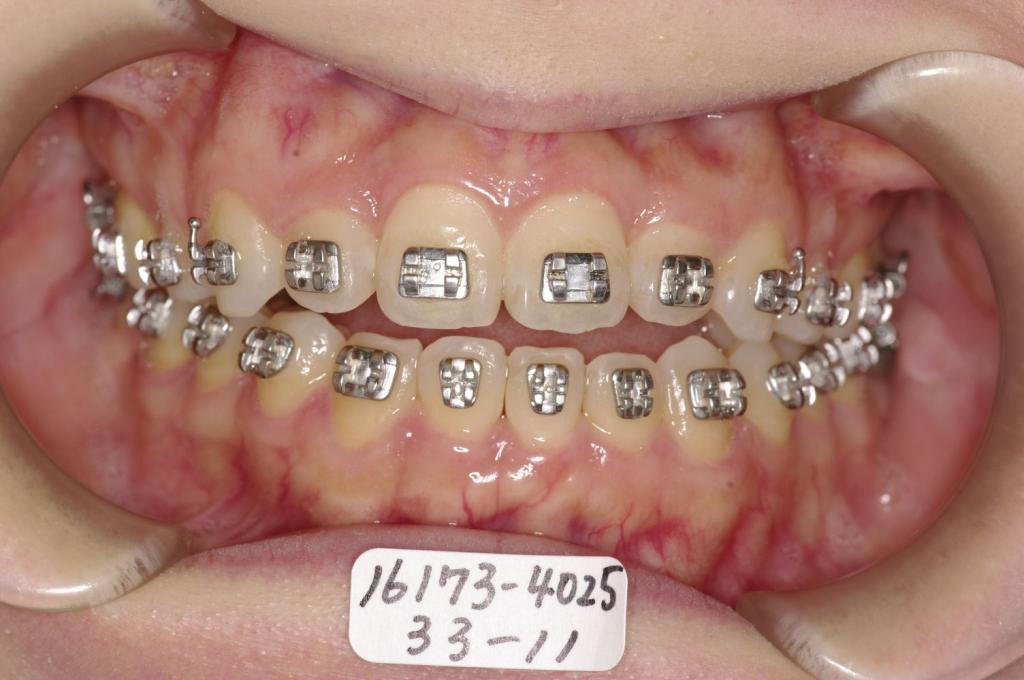

- 顎、顔の歪みの矯正治療

- 息がし難い